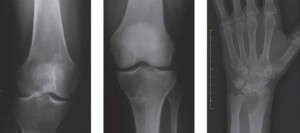

تومور سلول غول پیکر استخوان تومور سلول غول پیکر استخوان (Giant cell tumor of bone) یا به اختصار GCT، معمولاً به سایر قسمتهای بدن گسترش